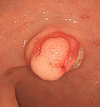

Calcifying fibrous tumor (CFT) is a recently recognized rare benign lesion characterized by dense hyalinized collagenous tissue with interspersed spindle cells and a lymphoplasmocytic infiltrate. Calcification is the hallmark of CFT and may present in the form of psammomatous bodies or dystrophic calcifications. CFT of the intestinal tract is uncommon and rectal CFT has never been reported. Recently, we experienced a case of CFT found in the rectum of a 36-year-old man. In this study, we described the characteristic histopathological findings with a review of the relevant literature. Although CFT of the intestinal tract as an intrinsic visceral lesion is unusual and clinically unexpected, CFT should be considered in the differential diagnosis of rectal submucosal tumor.